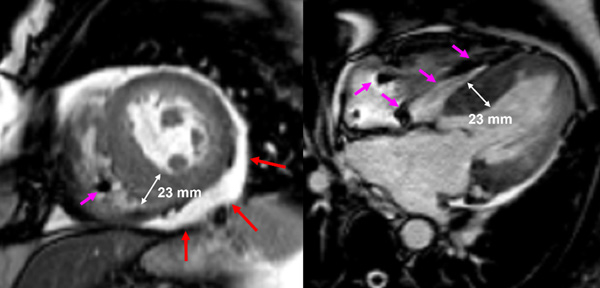

- Présence d’une hypertrophie ventriculaire gauche (HVG) asymétrique à prédominance septale mesurée au maximum à 23 mm.

- Visualisation de la sonde de PM avec artéfacts métalliques modérés au niveau du ventricule droit (flèches roses).

- Présence d’un épanchement péricardique de moyenne abondance (flèches rouges).